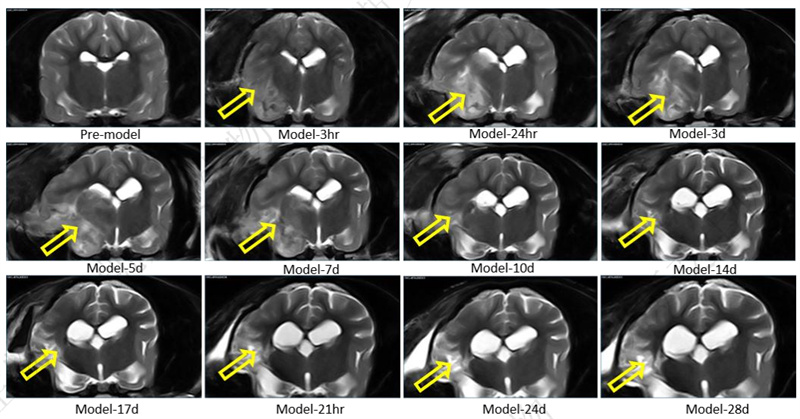

• 不同缺血时间,脑MRI影像变化:T2 2D FSE Dor

• 脑MRI影像变化